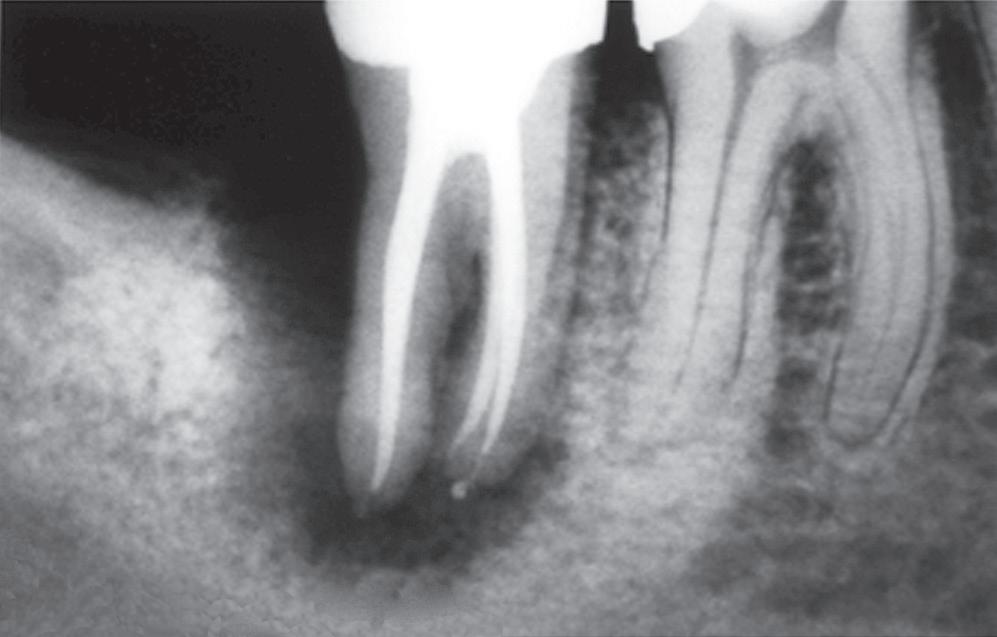

Periapical tissues can be mechanically irritated and inflamed by impact trauma, hyperocclusion, overinstrumentation of root canals, perforation of the root, and overextension of root canal filling materials (Fig. 1.4). Inaccurate determination of root canal length is usually the cause of overinstrumentation and subsequent inflammation. In addition, lack of an adequate apical resistance form created during cleaning and shaping can cause overextension of filling materials into the periapical tissues, causing physical and chemical damage (Fig. 1.5).

• Fig. 1.5 Improper instrumentation and extrusion of filling materials into the periapical tissues causes periradicular inflammation (arrows).